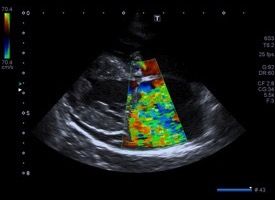

Modalità Doppler

Le misurazioni Doppler delle velocità di flusso sanguigno si basano sull’effetto Doppler. Il trasduttore genera degli ultrasuoni che vengono poi riflessi con una nuova frequenza, a seconda della velocità vettoriale delle particelle sanguigne, rilevata e rielaborata matematicamente in modo da ottene…